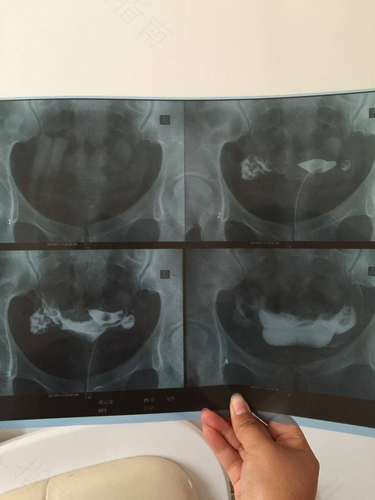

生活中,有些人生一胎的时候没有问题,但是在备孕二胎的时候比较吃力,由于担心是输卵管不通,就想去做输卵管造影。做输卵管造影的时候是有条件的,那么外阴痒能做输卵管造影吗?

外阴痒是不能做输卵管造影的,因为做了检查会引起细菌的上行感染,加重病情。女性需要去医院检查一下白带常规和妇科检查,明确病因以后,根据病因来进行治疗。在生殖道没有炎症之后,就可以去医院做输卵管造影了。